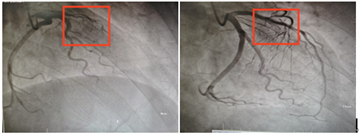

左图方框内为前降支闭塞部位,右图方框内为开通闭塞血管后影像。